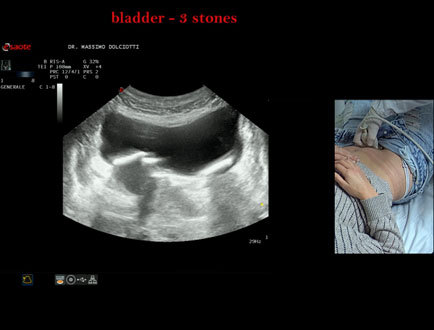

Motivazione dell'esame: da alcuni mesi, disuria ed infezioni urinarie recidivanti.

Commento all'esame: le immagini ed il video documentano 3 immagini iperecogene, con cono d'ombra posteriore, da ricondurre a litiasi multipla della vescica.

Conclusioni: 3 calcoli della vescica (3 bladder stones).